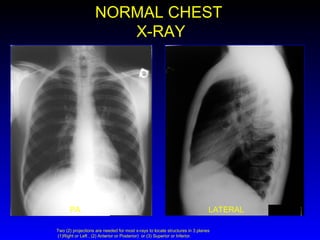

NORMAL CHEST X-RAY PA LATERAL Two (2) projections are needed for most x-rays to locate structures in 3 planes  (1)Right or Left , (2) Anterior or Posterior)  or (3) Superior or Inferior.

• #5 Two (2) projections are needed for most x-rays to locate structures in 3 planes (1)Right or Left , (2)Anterior or Posterior) or (3) Superior or Inferior.